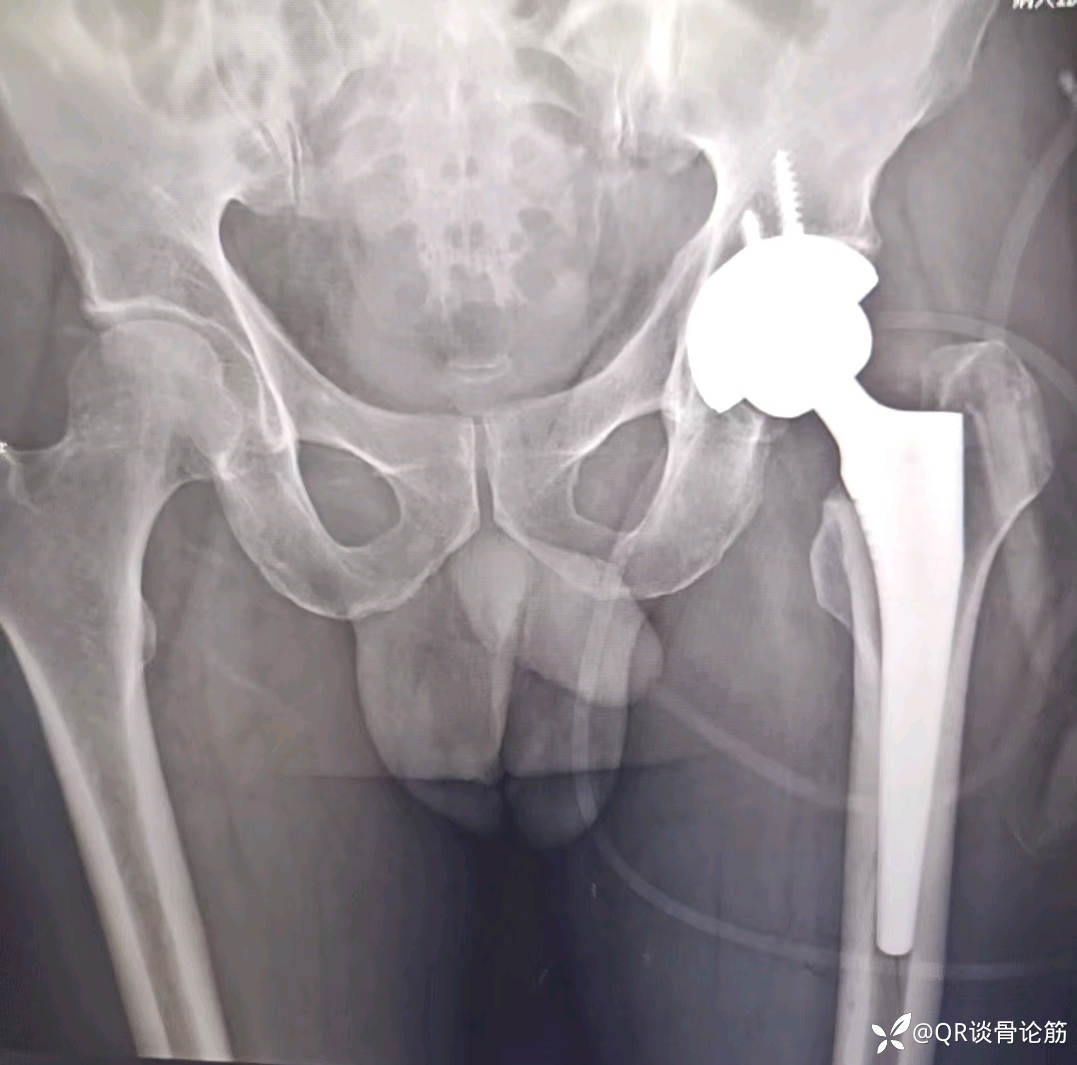

髋关节置换术中假体骨折了吗?

【治疗经过及结果】:第二天行全髋关节置换术

求有经验的老师给予指点,红色箭头标记处是否骨折了,如何处理 ,求助髋关节置换股骨侧假体术中骨折具体分型及处理。